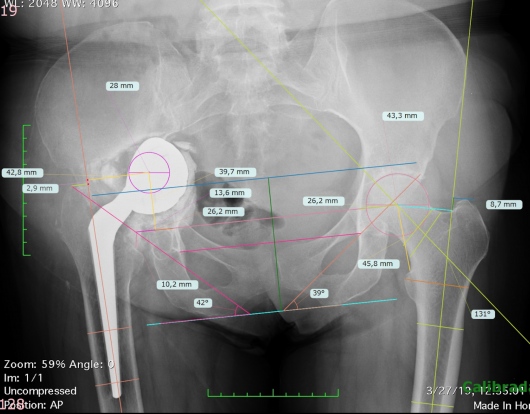

Practico una ortopedia centrada en usted como paciente, moderna, mínimamente invasiva y basada en evidencia científica. Me mantengo en constante actualización nacional e internacional y estoy certificado en cirugía de reemplazo articular con asistencia robótica con el sistema Mako® de Stryker, una tecnología de última generación para el reemplazo de cadera y rodilla, la más avanzada de Latinoamérica y el mundo.

Gracias a la planificación quirúrgica en modelos tridimensionales personalizados, este sistema permite una precisión milimétrica, lo que se traduce en:

Menor dolor postoperatorio

Incisiones más pequeñas

Mayor estabilidad de la prótesis

Recuperación funcional más rápida

Menor tasa de reintervención

Para lograr los mejores resultados, realizo mis procedimientos quirúrgicos en el Hospital Internacional de Colombia (HIC). Esta institución cuenta con la acreditación de la Joint Commission International (JCI), un sello de excelencia que solo poseen los mejores hospitales del mundo y que garantiza que usted recibirá atención bajo los más estrictos estándares globales de seguridad y calidad hospitalaria.

Artroplastia de la cadera